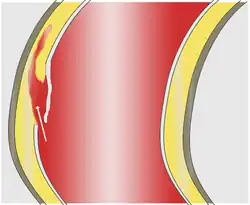

Blood penetrates the intima and enters the media layer.

As with all other arteries, the aorta is made up of three layers, the intima, the media, and the adventitia. The intima is in direct contact with the blood inside the vessel, and mainly consists of a layer of endothelial cells on a basement membrane; the media contains connective and muscle tissue, and the vessel is protected on the outside by the adventitia, comprising connective tissue.[26]

In an aortic dissection, blood penetrates the intima and enters the media layer. The high pressure rips the tissue of the media apart along the laminated plane splitting the inner two-thirds and the outer one-third of the media apart.[27] This can propagate along the length of the aorta for a variable distance forward or backward. Dissections that propagate towards the iliac bifurcation (with the flow of blood) are called anterograde dissections and those that propagate towards the aortic root (opposite of the flow of blood) are called retrograde dissections. The initial tear is usually within 100 mm of the aortic valve, so a retrograde dissection can easily compromise the pericardium leading to a hemopericardium. Anterograde dissections may propagate all the way to the iliac bifurcation of the aorta, rupture the aortic wall, or recanalize into the intravascular lumen leading to a double-barrel aorta. The double-barrel aorta relieves the pressure of blood flow and reduces the risk of rupture. Rupture leads to hemorrhaging into a body cavity, and prognosis depends on the area of rupture. Retroperitoneal and pericardial ruptures are both possible.[28]

The initiating event in aortic dissection is a tear in the intimal lining of the aorta. Due to the high pressures in the aorta, blood enters the media at the point of the tear. The force of the blood entering the media causes the tear to extend. It may extend proximally (closer to the heart) or distally (away from the heart) or both. The blood travels through the media, creating a false lumen (the true lumen is the normal conduit of blood in the aorta). Separating the false lumen from the true lumen is a layer of intimal tissue known as the intimal flap.

The vast majority of aortic dissections originate with an intimal tear in either the ascending aorta (65%), the aortic arch (10%), or just distal to the ligamentum arteriosum in the descending thoracic aorta (20%).

As blood flows down the false lumen, it may cause secondary tears in the intima. Through these secondary tears, the blood can re-enter the true lumen.